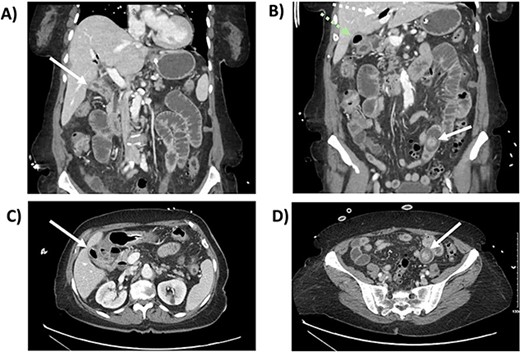

She underwent a diagnostic laparoscopy revealing a transition point secondary to the impacting 3-cm gallstone in the mid-jejunum. A small laparotomy was used to perform an enterotomy, stone extraction, and enterotomy closure. She had an unremarkable postoperative course. After 2 months, a follow-up CT revealed pneumobilia and a likely cholecystoduodenal fistula (Fig. 2). After medical optimization, she was scheduled for an elective robotic cholecystectomy and repair of the fistula 7 months later.

CT scan from follow-up after the index procedure. A) Axial CT: cholecystoduodenal fistula; air-filled gallbladder (superior, green arrow), duodenum (inferior, white arrow), B) Axial CT: air-filled gallbladder (superior, green arrow), duodenum (inferior, white arrow), C) Coronal CT: cholecystoduodenal fistula; air-filled gallbladder (superior,green arrow), duodenum (inferior, white arrow), D) Coronal CT: air-filled gallbladder (superior, green arrow), duodenum (inferior, white arrow).